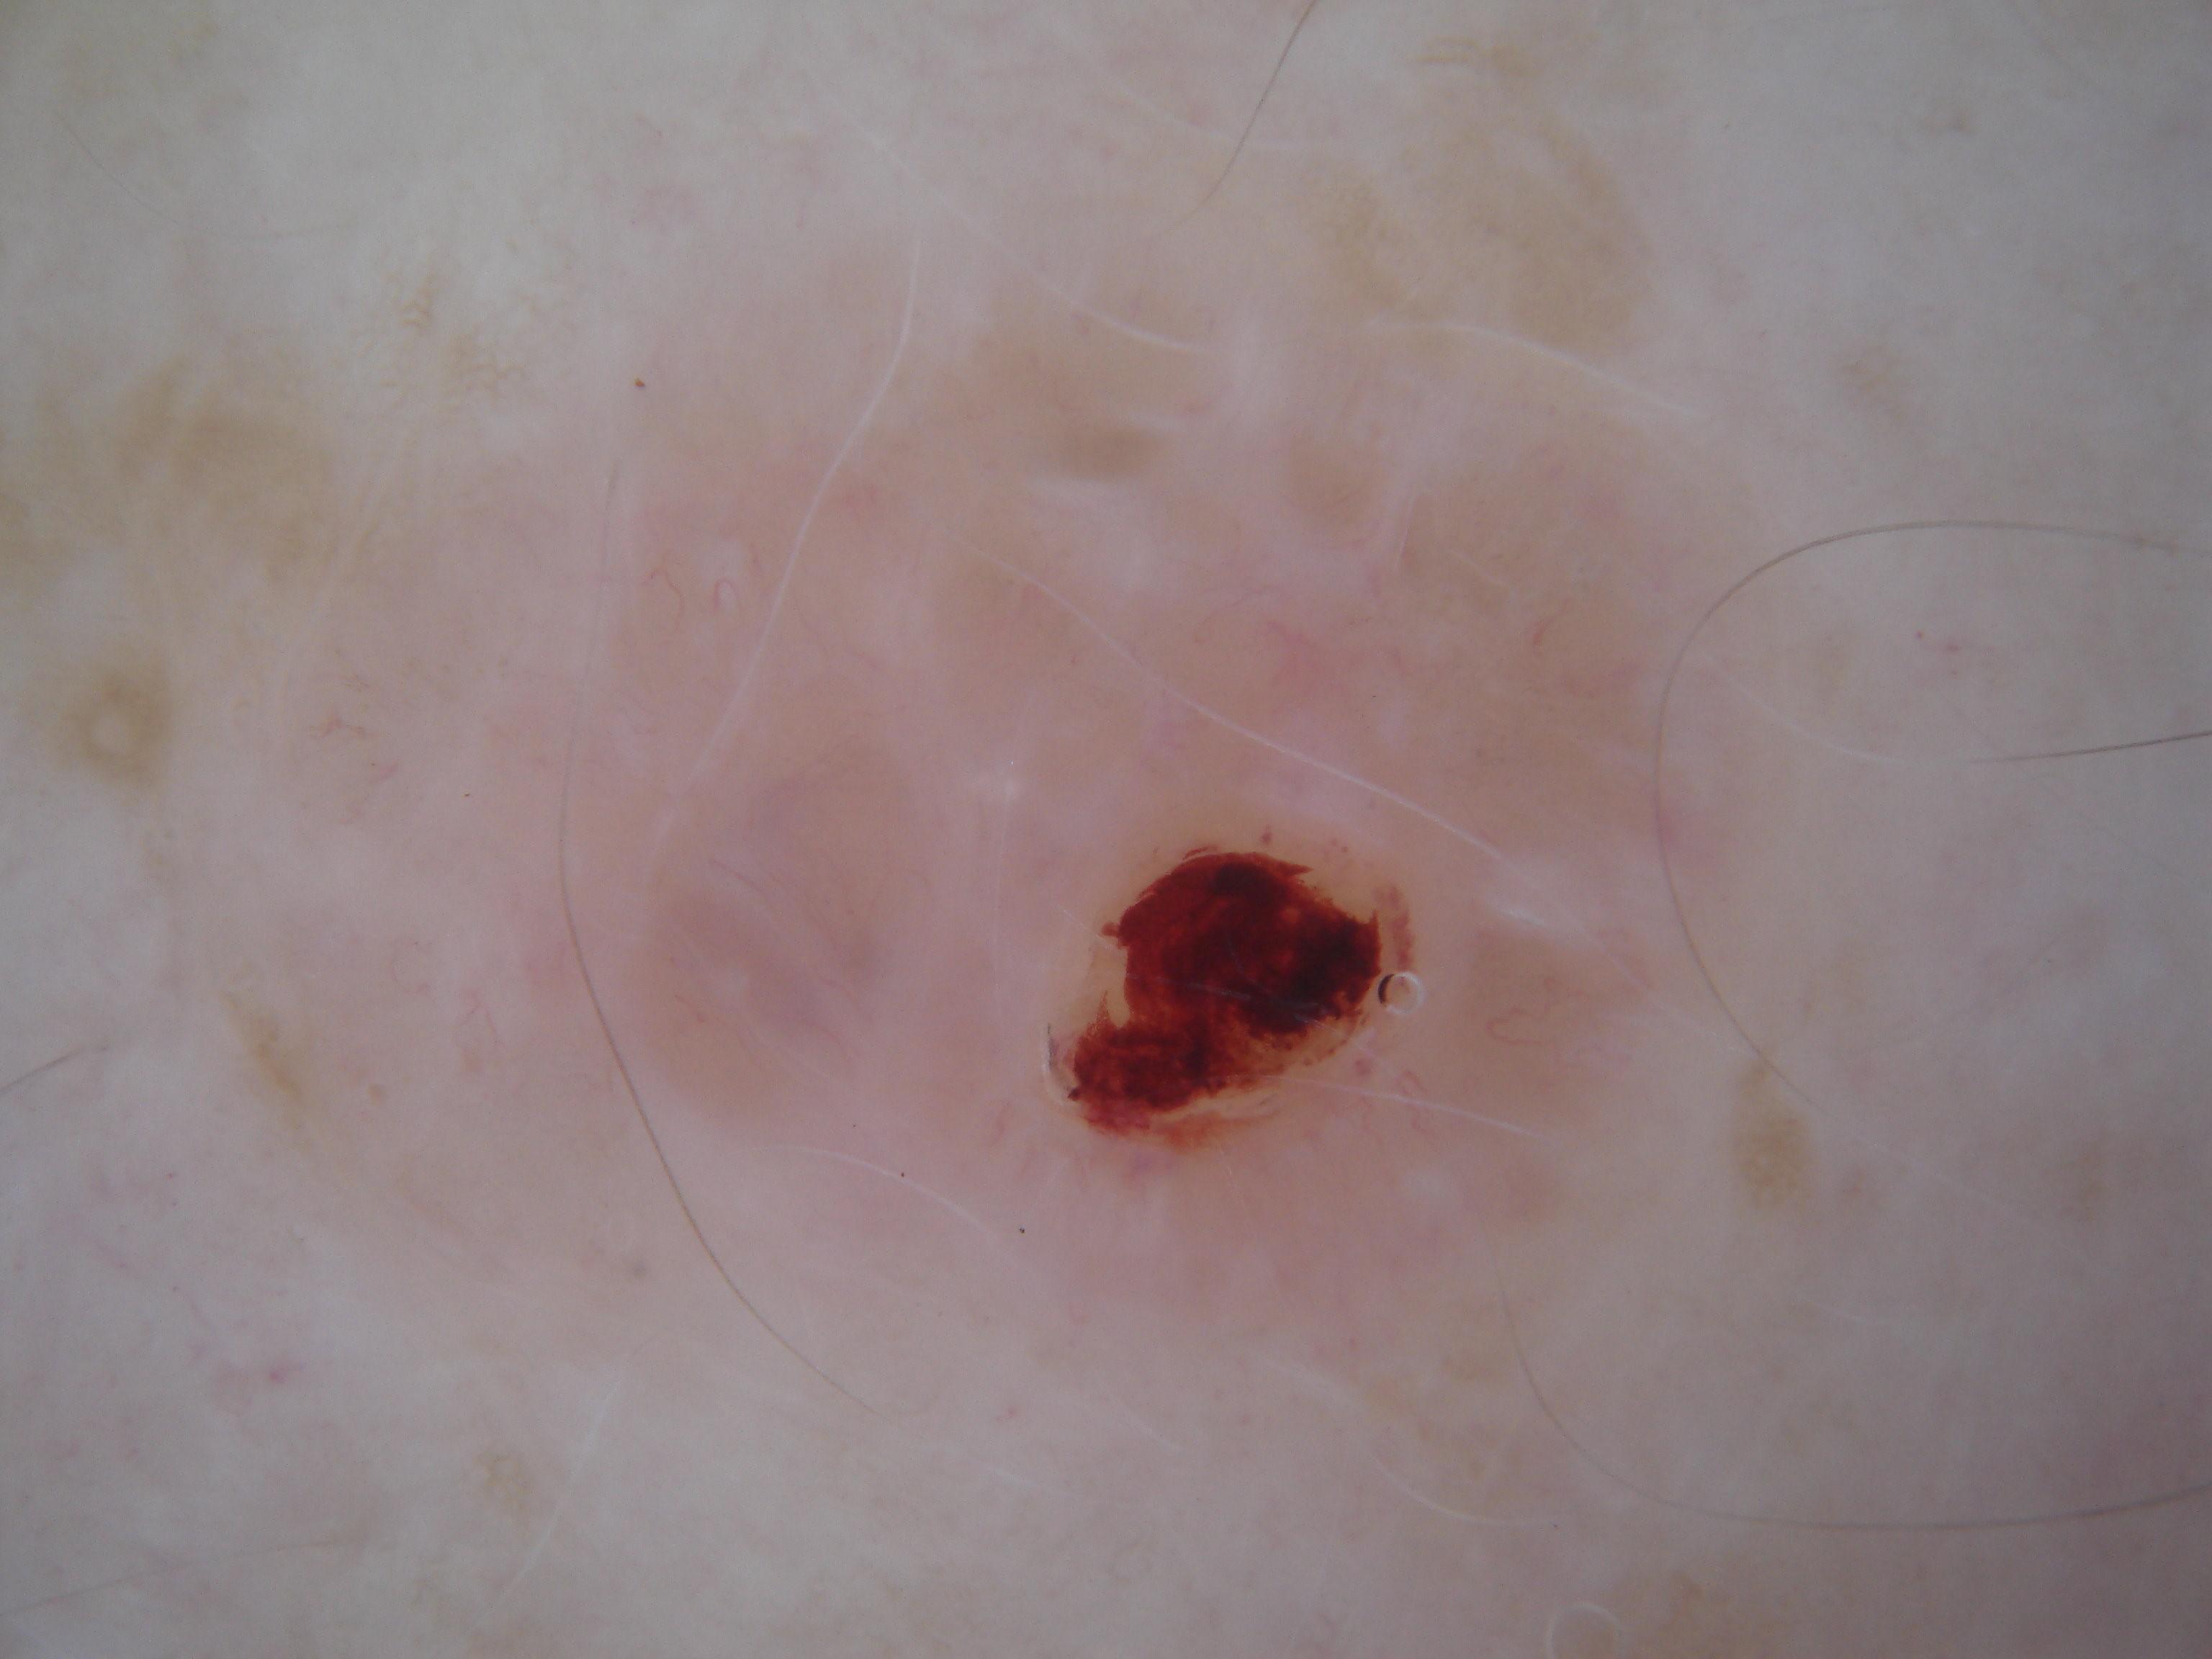

{

"age_approx": 35,

"anatom_site_general": "lower extremity",

"concomitant_biopsy": true,

"dermoscopic_type": "contact polarized",

"diagnosis_1": "Malignant",

"diagnosis_2": "Malignant melanocytic proliferations (Melanoma)",

"diagnosis_3": "Melanoma Invasive",

"diagnosis_confirm_type": "histopathology",

"family_hx_mm": false,

"image_type": "dermoscopic",

"mel_thick_mm": "0.31",

"mel_ulcer": false,

"melanocytic": true,

"patient_id": "IP_2139998",

"personal_hx_mm": false,

"sex": "male"

}